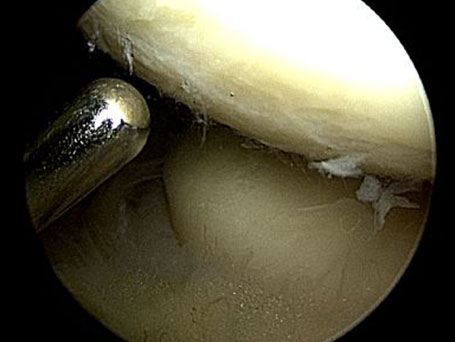

Ähnlich wie beim Kniegelenk oder beim Schultergelenk behandeln wir auch das Ellenbogengelenk arthroskopisch. Über kleine Zugänge wird das Gelenk mit einer fiberoptischen Kamera untersucht. Dabei ist das Ellenbogengelenk in zwei Abschnitten arthroskopisch angehbar. Zunächst wird für den vorderen Gelenkabschnitt in der Ellenbeuge ein außenseitiges und ein innenseitiges Portal angelegt. Hier lässt sich das Speichenköpfchen und die vorderen Abschnitte der Oberarmrolle und der Kronenfortsatz der Elle einsehen. Entzündungen der Gelenkschleimhaut und insbesondere Verdickungen der Gelenkschleimhautfalte am Speichenköpfchen können so erkannt und entfernt werden. In einem zweiten Abschnitt kann dann der hintere Anteil des Gelenkes rund um den Ellenhaken eingesehen werden (Fossa olecrani).

Freie Gelenkkörper können ebenso beseitigt werden wie Knochenvorsprünge, die zu Bewegungseinschränkungen führen, Knorpelschäden in den einzelnen Gelenkabschnitte lassen sich gut inspizieren und behandeln.

Ellenbogenarthroskopie: Oberarmrolle und Speichenköpfchen

Ellenbogengelenksarthroskopie

Arthroskopie-Ellenbogen